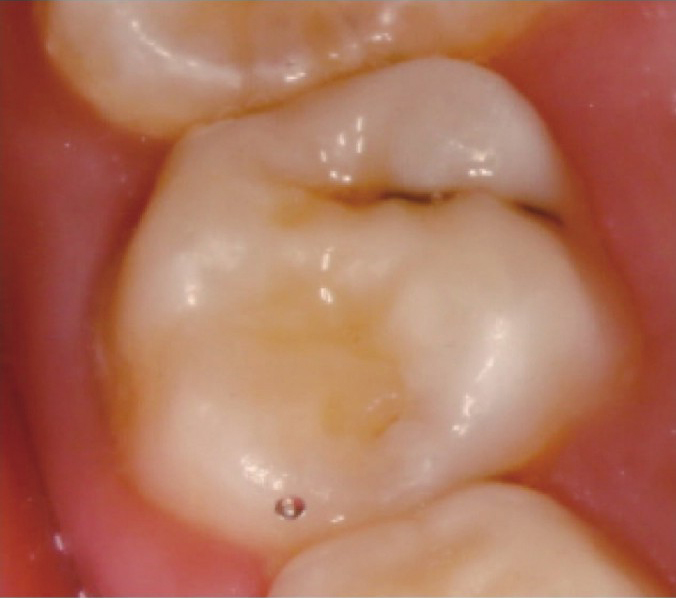

需要封闭的窝沟已经发生龋坏(图2-2)。

图2-2 窝沟已经发生龋坏的恒磨牙 L9QOUQiQGcUpqewL+QzmJ7tkyacI9f171hMMe5QPgXFSlXBfARH9KiTkNELJvqF4